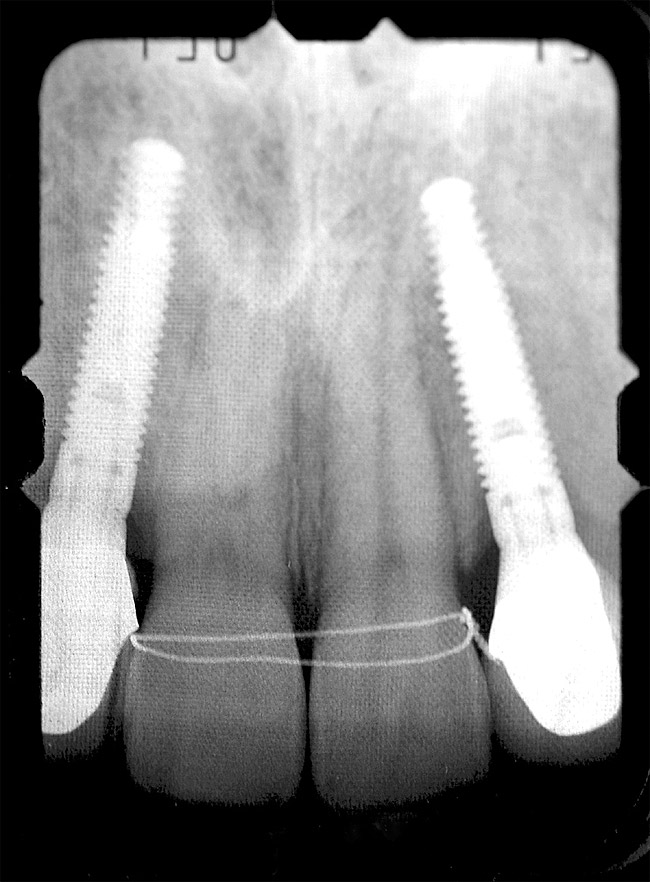

Periapical radiographs were taken to help determine the mesial-distal inclinations of the adjacent tooth roots (Figure 1). The radiographs revealed a serious issue, convergent roots for the right canine and right central, which eliminated that area as a potential implant-receptor site. The space between the left central and canine teeth was minimal, although the roots were relatively parallel. Clinical examination (manual palpation of the root eminences superiorly to the vestibule on the right side) confirmed the root convergence (Figure 2A). The flat, wide zone of the keratinized tissue and lack of interdental papilla was evident for the missing right lateral incisor. There was a marked difference in clinical appearance for the left lateral, which could impact the eventual plan of treatment (Figure 2B). Other significant clinical findings included bilateral facial bone concavities, which existed as a result of the congenitally missing tooth roots. As a diagnostic cue to the underlying bone topography, it is important to follow the demarcation between attached and unattached gingival tissue, and note the crestal width of the available keratinized tissue (Figure 2C).

Based upon the intraoral examination and periapical radiographs, additional orthodontic intervention was r.commended to move and rotate the roots to gain enough space for implant placement. This information was conveyed to both the parents and to the treating orthodontist. After several additional months, a panoramic radiograph was provided by the orthodontist to evaluate the distance between the clinical crowns and tooth roots (Figure 3). The lack of sharpness, definition, and radiographic artifacts made it impossible to determine whether implants could be successfully placed based on the 2D panoramic image. This diagnostic predicament was discussed with the patient and his parents, and it was suggested that a CT scan would be necessary to accurately assess the bone topography and spatial orientation of the adjacent roots. The parents agreed, and the patient was given a prescription for a CT scan study at a local radiology center.

Figure 1  Pretreatment radiographs revealed convergent roots for the right canine and right central.

Figure 1